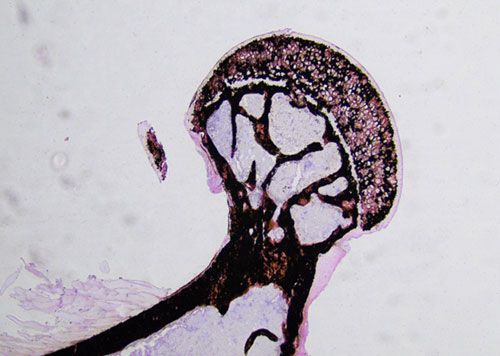

骨組織中含有大量沉積性鈣鹽。利用未脫鈣骨硬組織包埋,制成硬組織切片,完整保留了骨組織中的鈣鹽。骨組織切片經XSY溶液處理,鈣被銀沉積置換,再經強光還原成可見的金屬銀,肉眼觀察為黑色,是一種比較理想的觀察骨組織中鈣鹽沉積的方法。

未脫鈣小鼠股骨von kossa染色

未脫鈣小鼠椎骨von kossa染色

切片脫塑-XSY反應蘇木素染色-伊紅染色-脫水封片-顯微鏡鏡檢